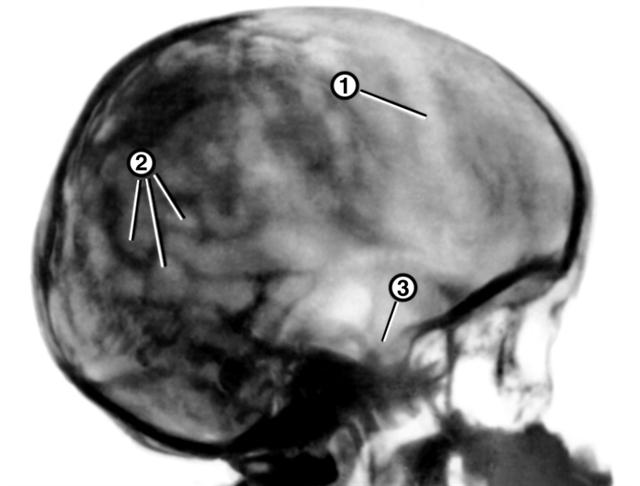

Рис. 3. Рентгенограмма черепа при окклюзионной гидроцефалии у ребенка 6 лет (боковая проекция): резко растянуты швы черепа (1), выражены пальцевые вдавления (2), истончена спинка турецкого седла (3).